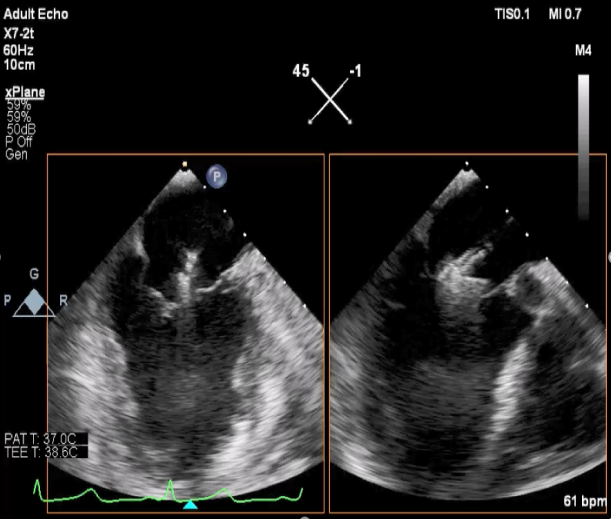

二尖瓣联合部切面引导第一枚XTR夹子转向病变区域并逐渐进入左室

第一枚XTR夹子到达病变区域捕获瓣叶并逐渐夹闭

XTR夹子释放,残余部分返流

三维超声心动图显示第一枚XTR夹子释放,残余返流主要位于外侧

引导第二枚XTR夹子转向外侧残余病变区域并逐渐进入左室

第二枚XTR夹子释放,返流明显减少

三维超声心动图显示第二枚XTR夹子释放